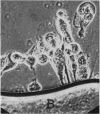

Images in this article